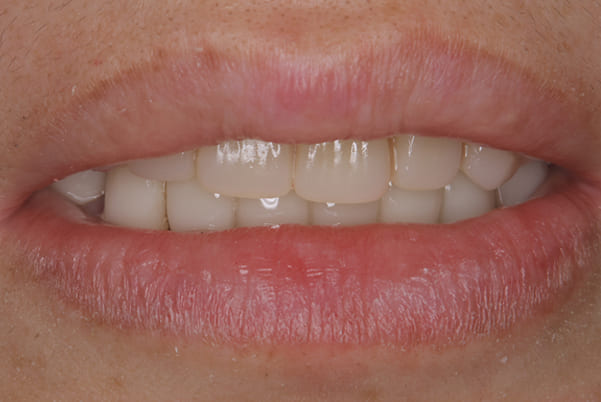

奥歯がなくなり、放置されたことで、かみ合わせが深く乱れた状態でした。

乱れたかみ合わせを治し、治療途中で見た目は患者様がご納得いく、歯の大きさ、色、形をご一緒に確認しながら入れ歯を最終的に作製しました。

-

上顎治療後

下顎治療後